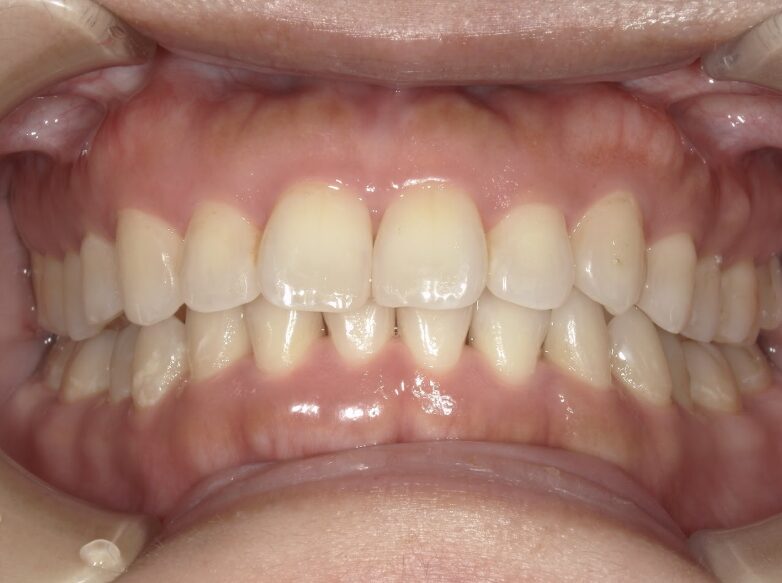

過蓋咬合

ガタガタを主訴に当院を受診され、上下前歯部に叢生(ガタガタ)と過蓋咬合(上の歯が下の歯を深く覆いかぶさっている状態)を認めました。

IPRを使用してマウスピース型矯正装置(インビザライン)を使用し過蓋咬合及び叢生の改善を行いました。

年齢/性別30代女性

抜歯部位非抜歯

治療期間1年6ヶ月